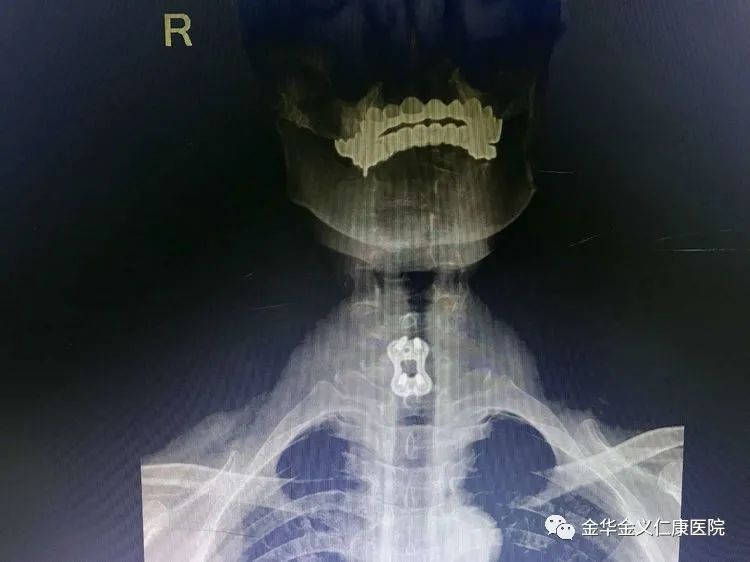

术后的X光片